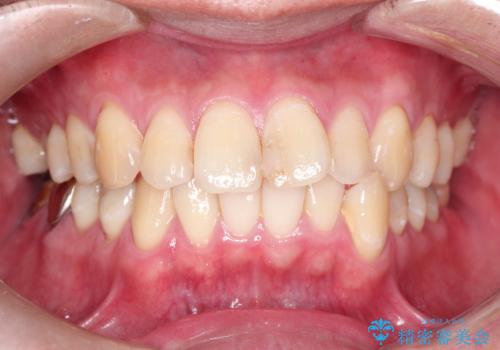

全体のすきっぱ マウスピース矯正~インビザライン~

- すきっぱが気になることを主訴にご来院された患者様です。

咬み合わせが深く、上下の正中もずれていたため、できる範囲でそれらも治す方針となりました。

インビザラインによるマウスピース矯正で治療することになりました。

今回の患者様は、舌壁(舌で前歯を押すくせ)があったため、すきっぱになっていました。そのため、舌の筋力トレーニングを指導しました。

また、矯正治療は一生に一度の治療になることがほとんどなので、咬み合わせや患者様が気付かない部分(正中のズレ)なども極力治していきます。(骨格などによる限界あり)